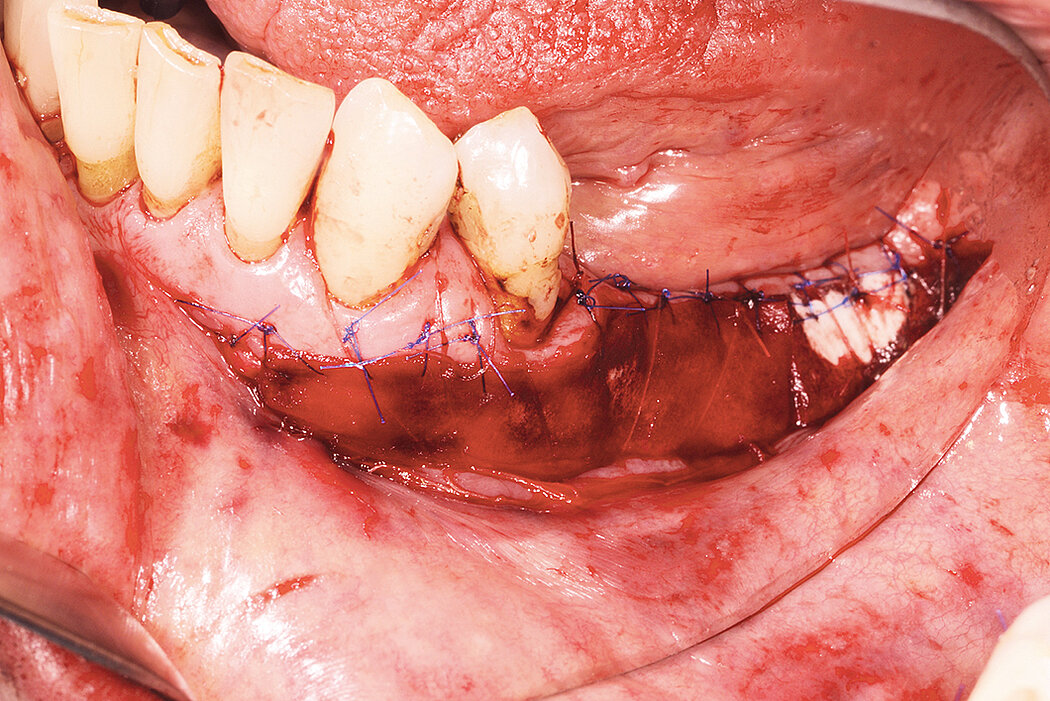

角化组织增宽

临床挑战

种植术前进行附着龈增宽

目标

复杂种植修复进行骨增量和种植术前,使用Geistlich Mucograft®进行附着龈增宽。

结论

使用Geistlich Mucograft® 可获得天然牙及种植体周围的附着龈增宽,和自体瓣移植相比,又因避免腭部创伤而大大降低了患者的不适,而且和周围组织的颜色更协调。异种胶原基质较游离龈移植瓣(FGG)的收缩率高,所以必须尽可能扩大术区以及保留更多的基质余量。